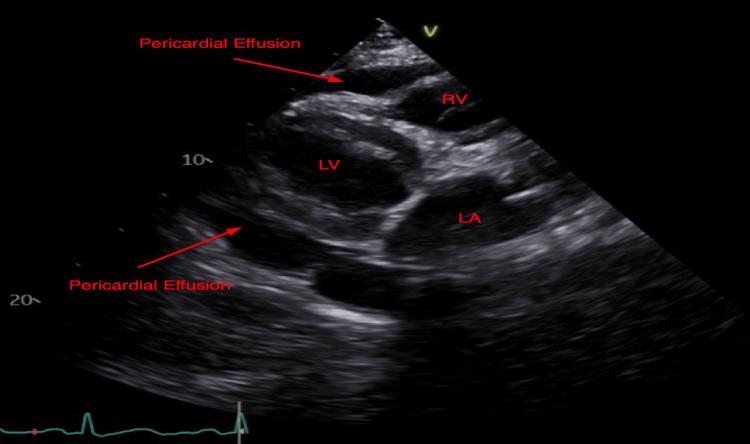

Familial Mediterranean fever (FMF) is a hereditary, autosomal recessive auto-inflammatory disorder characterized by recurrent attacks of fever and serositis. While arthritis, pleuritis, peritonitis, and pericarditis are common in FMF, large pericardial effusions with cardiac tamponade as a sequelae of FMF are considered rare.  We report a case of an 83-year-old female with a history of FMF who presented with chest pain. She was found to have acute pericarditis complicated by hemodynamically significant pericardial tamponade that was subsequently treated with an urgent pericardiocentesis followed by colchicine.

家族性地中海热(FMF)是一种遗传性常染色体隐性自身炎症性疾病,其特征为反复发热和浆膜炎发作。虽然关节炎、胸膜炎、腹膜炎和心包炎在FMF中很常见,但作为FMF后遗症的伴有心脏压塞的大量心包积液被认为很罕见。我们报告一例83岁有FMF病史的女性,她因胸痛就诊。发现她患有急性心包炎并伴有血流动力学显著的心包压塞,随后接受了紧急心包穿刺术并服用秋水仙碱进行治疗。